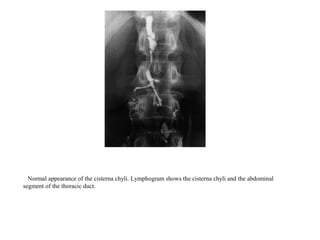

Normal appearance of the cisterna chyli. Lymphogram shows the cisterna chyli and the abdominal

segment of the thoracic duct.

Normal appearance ofthe cisterna chyli. Lymphogram shows the cisterna chyli and the abdominal segment of the thoracic duct.